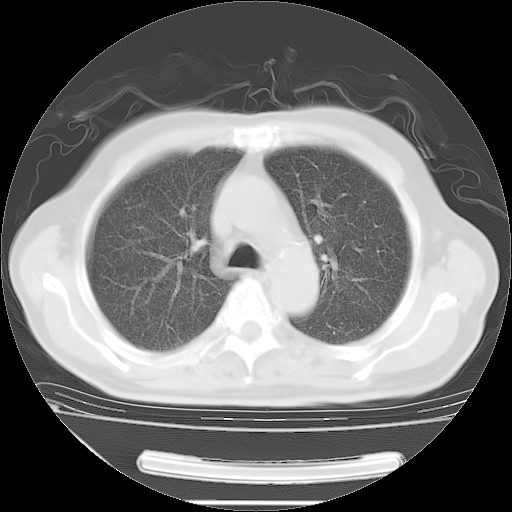

今天复查肺部CT,发现双肺广泛磨玻璃样改变。所以我把3月19日和5月9日相隔50天的肺部CT上传。请大家会诊。

2009年3月19日肺部CT片。

2009年3月19日肺部CT